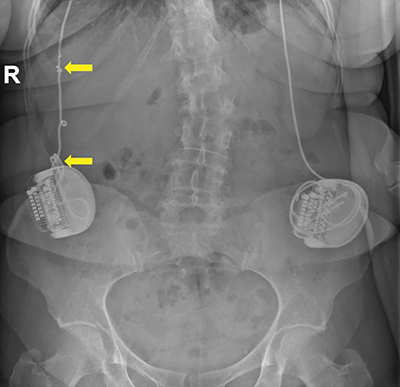

Teaching point: Twiddler's syndrome is a very rare but potentially disastrous complication after implantation of a neurostimulator or pacemaker, caused by twisting of the generator within the subcutaneous pocket, resulting in dislodgement and/or interruption of the electrodes that should be reported on x-ray.